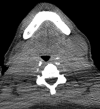

Purpose: To assess the feasibility of combined electromagnetic device tracking and computed tomography (CT)/ultrasonography (US)/fluorine 18 fluorodeoxyglucose (FDG) positron emission tomography (PET) fusion for real-time feedback during percutaneous and intraoperative biopsies and hepatic radiofrequency (RF) ablation.

Materials and methods: In this HIPAA-compliant, institutional review board-approved prospective study with written informed consent, 25 patients (17 men, eight women) underwent 33 percutaneous and three intraoperative biopsies of 36 FDG-avid targets between November 2007 and August 2010. One patient underwent biopsy and RF ablation of an FDG-avid hepatic focus. Targets demonstrated heterogeneous FDG uptake or were not well seen or were totally inapparent at conventional imaging. Preprocedural FDG PET scans were rigidly registered through a semiautomatic method to intraprocedural CT scans. Coaxial biopsy needle introducer tips and RF ablation electrode guider needle tips containing electromagnetic sensor coils were spatially tracked through an electromagnetic field generator. Real-time US scans were registered through a fiducial-based method, allowing US scans to be fused with intraprocedural CT and preacquired FDG PET scans. A visual display of US/CT image fusion with overlaid coregistered FDG PET targets was used for guidance; navigation software enabled real-time biopsy needle and needle electrode navigation and feedback.

Results: Successful fusion of real-time US to coregistered CT and FDG PET scans was achieved in all patients. Thirty-one of 36 biopsies were diagnostic (malignancy in 18 cases, benign processes in 13 cases). RF ablation resulted in resolution of targeted FDG avidity, with no local treatment failure during short follow-up (56 days).

Conclusion: Combined electromagnetic device tracking and image fusion with real-time feedback may facilitate biopsies and ablations of focal FDG PET abnormalities that would be challenging with conventional image guidance.